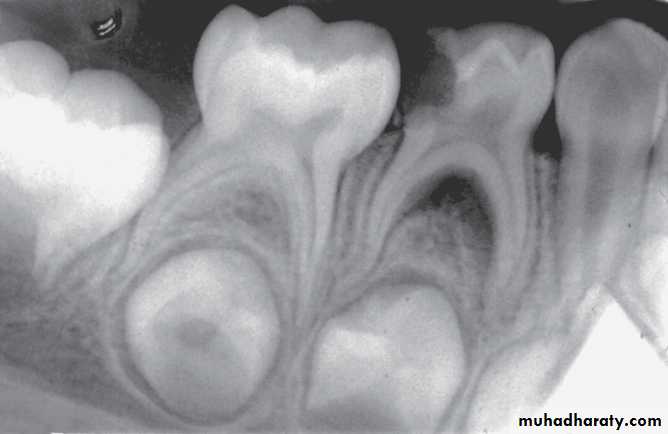

Internal resorption after calcium hydroxide pulpotomy in a primary tooth

Deep caries in the first primary molar and due to that caries resorption in the bifurcation areaDeep caries in the mandibular second primary molar

Periapical radiographs

Infected mandibular second primary molar

has caused hypoplasia of the second premolar and delayed eruption of the tooth.Pre-eruptive “caries” on the crown of an

unerupted first premolar (arrow).